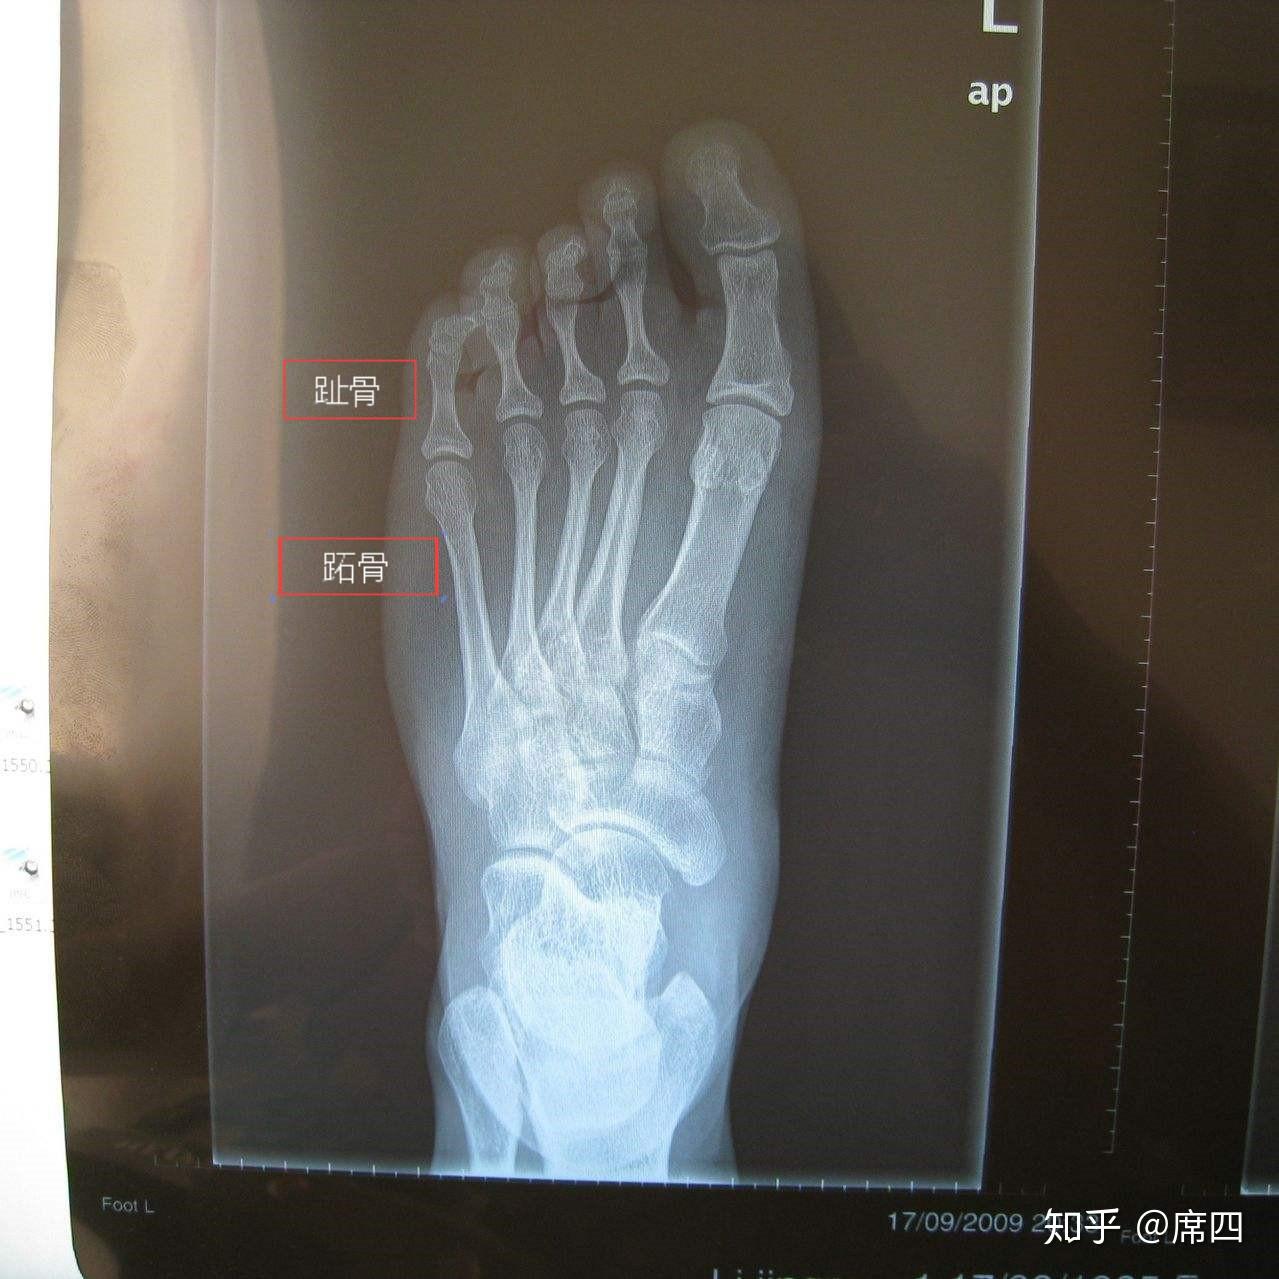

第四跖骨怎么了,(如图)请会诊,谢谢!